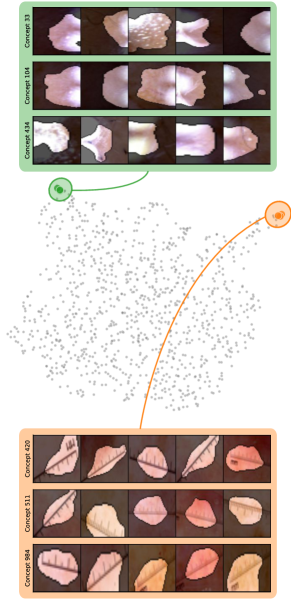

Model Perspective

Next, we apply bias identification approaches from the model perspective by identifying outlier neurons based on activation pattern via DORA and relevance pattern by clustering pair-wise cosine distances between concept relevance scores. We focus on latent activations and relevances after the third residual block. DORA uses a distance function based on how neurons activate upon each others n-AMS, achieving high similarity when neurons activate upon similar input signal. A 2D visualization of the resulting distance matrix is shown in Fig. 6 (bottom left). Identified outlier concepts include ruler () and (white) hair (). We further compute pairwise cosine distances between latent relevance scores , aggregated over spatial dimensions, and apply UMAP to embed the resulting distance matrix in . This results in high similarity between neurons (concepts) that the model uses similarly for predictions. The concept clustering is visualized in Fig. 6 (bottom right), highlighting two outlier clusters focused on rulers () and blueish tint ().

Results for other classes, model architectures, and datasets are presented in Appendix A.6.1. This includes experiments with ECG data in Fig. 10, revealing the artificially inserted static noise in the attacked lead from both data and model perspectives. Notably, dominant spurious concepts, such as the artificial timestamp in HyperKvasir or the static noise in PTB-XL, may not be detected as outlier concepts. In such cases, analyzing prediction sub-strategies via PCX may provide additional insights on spurious inlier behavior. Hard-to-interpret concept representations pose another challenge for the model perspective. For example, the brightness artifact in CheXpert is not clearly visible in the concept UMAP (see. Fig. 15, right), but can easily be detected using SpRAy (Fig. 15, left) or PCX (Fig. 22). In summary, while all considered spurious features are detected, the choice of bias identification approach is crucial, as some shortcuts are easier to detect as outlier concept (e.g., ruler) and others via PCX (e.g., brightness, static noise in ECG).